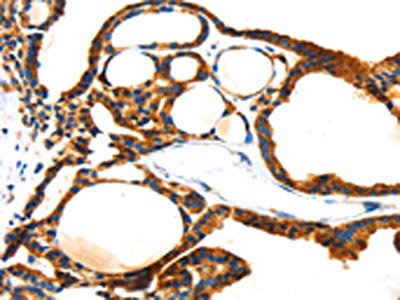

The image on the left is immunohistochemistry of paraffin-embedded Human liver cancer tissue using CSB-PA273921(TBX18 Antibody) at dilution 1/20, on the right is treated with fusion protein. (Original magnification: ×200)

The image on the left is immunohistochemistry of paraffin-embedded Human thyroid cancer tissue using CSB-PA273921(TBX18 Antibody) at dilution 1/20, on the right is treated with fusion protein. (Original magnification: ×200)